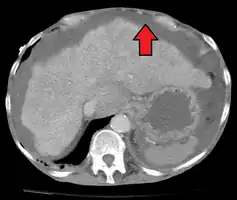

Ultrasound investigation is often performed prior to attempts to remove fluid from the abdomen. This may reveal the size and shape of the abdominal organs, and Doppler studies may show the direction of flow in the portal vein, as well as detecting Budd-Chiari syndrome (thrombosis of the hepatic vein) and portal vein thrombosis. Additionally, the sonographer can make an estimation of the amount of ascitic fluid, and difficult-to-drain ascites may be drained under ultrasound guidance. An abdominal CT scan is a more accurate alternate to reveal abdominal organ structure and morphology.

• Grade 1: mild, only visible on ultrasound and CT